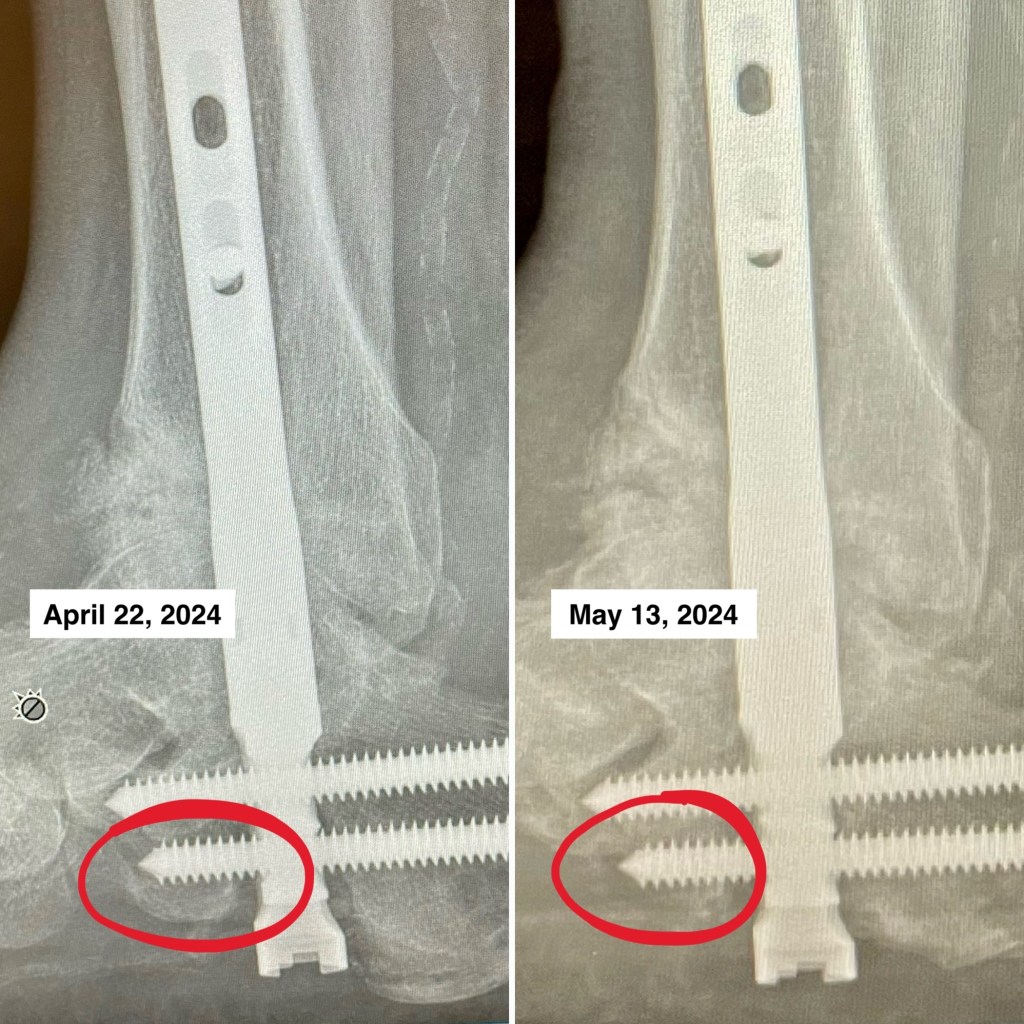

Ankle Update 20240513

I saw the orthopedic surgeon this morning and there is potential bad news. It is difficult to see but it appears that I am losing bone from the tip of one of the screws in my foot. I made a composite of photos I took of x-rays.

There is definitely more bone in the April picture and just a shadow from this morning. The surgeon wants me to get a CT scan for a clearer image. He also went to consult with the other foot/ankle surgeon in his office, and both are uncertain what it could be. He did suggest Charcot Foot, which would fit since I am diabetic, but why so much change in three weeks? I was told to stop physical therapy until after he sees the CT scan.

If the bone is indeed deteriorating, one solution is to remove the bottom screw from my foot. We need to make sure that the ankle is properly fused to the metal rod. That would require another surgery, but it would be relatively minor and require much less recovery. Still sucks though.